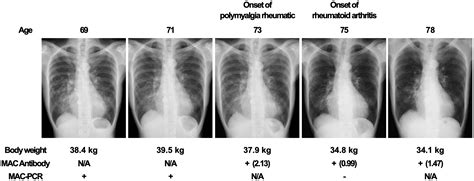

Diagnosing Mac Lung Disease involves a combination of clinical evaluation, laboratory tests, and imaging studies. The diagnostic process typically includes:

• Imaging Studies: Imaging tests like X-rays, CT scans, or MRIs to assess organ involvement and detect any abnormalities.